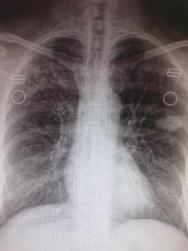

疾病检查

陈旧性肺结核陈旧性肺结核胸片。

诊断鉴别

陈旧性肺结核陈旧性肺结核根据胸片可确诊。